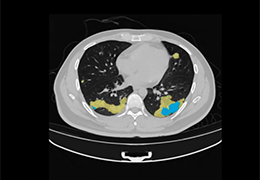

成像智能。

Eclipse 成像智能功能提供强大的处理能力和最佳质量的影像,同时减少质量错误并提高剂量效率。

凭借 AI、专有算法和先进的影像处理能力,提供出色的影像质量和无与伦比的诊断信心。

与标准影像处理相比,智能降噪功能可使客户降低辐射剂量,而不会损失影像质量。这在新生儿和儿科成像中尤其重要,在这种情况下以尽可能低的剂量成像至关重要。